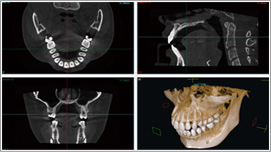

当院では精度の高い治療を行うために、最新鋭CTスキャンを導入しております。

従来のレントゲン画像は平面像(二次元)でしたが、歯科用CT画像は立体画像(三次元)で表すことが可能です。

例えば、インプラント治療の際に、顎の骨の状態(質や厚み、高さ、形態など)を把握することができ、顎の内部構造(骨の高さ・厚みや神経、血管の位置)を立体的に確認することができ、より正確な診断が可能となりました。

CTは、歯だけでなく、顎の内部構造や上顎洞の形態、粘膜の状態、病巣などを立体画像で確認できるので、いままでわかりにくかったところも見落とすことなく、治療することができます。